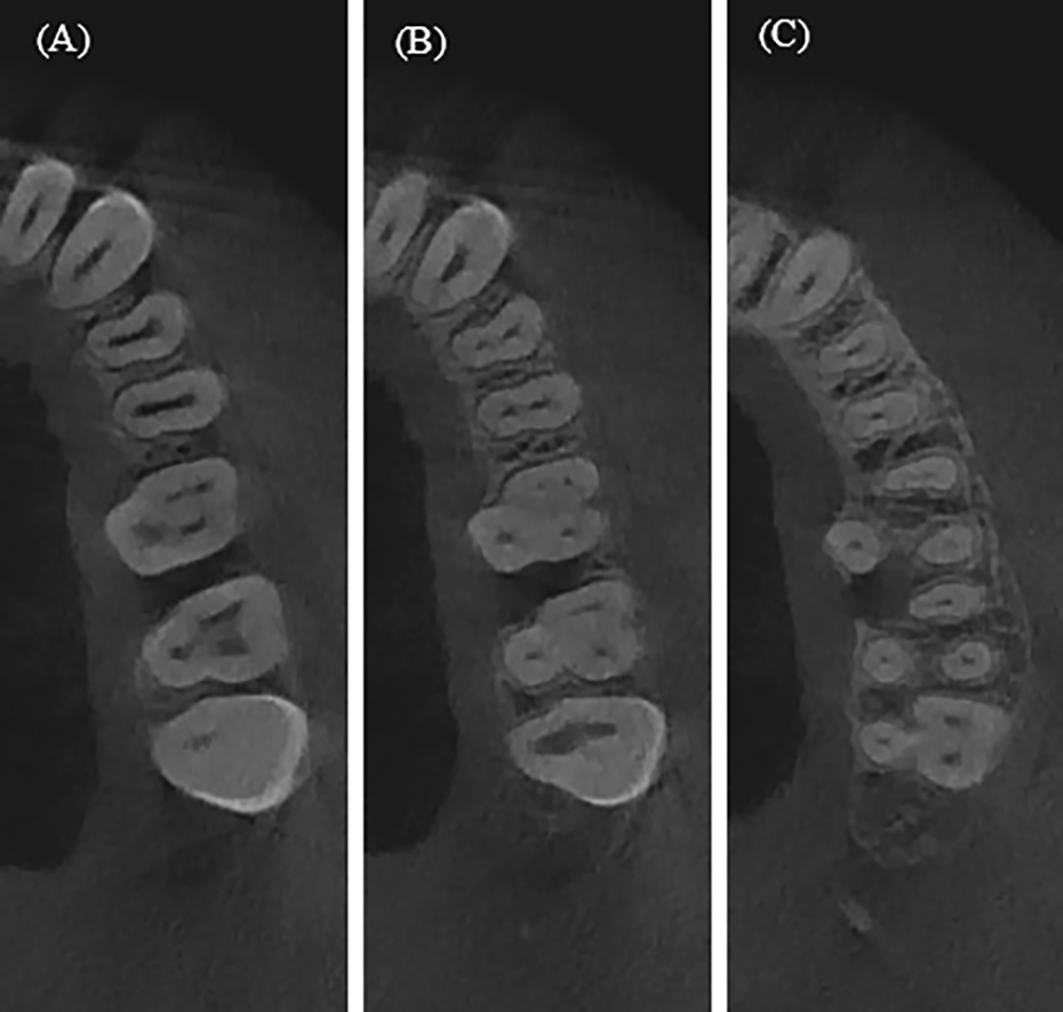

Cross-sectional root canal shape of maxillary premolar and molars, (A) Coronal third, (B) Middle Third, (C) Apical third.